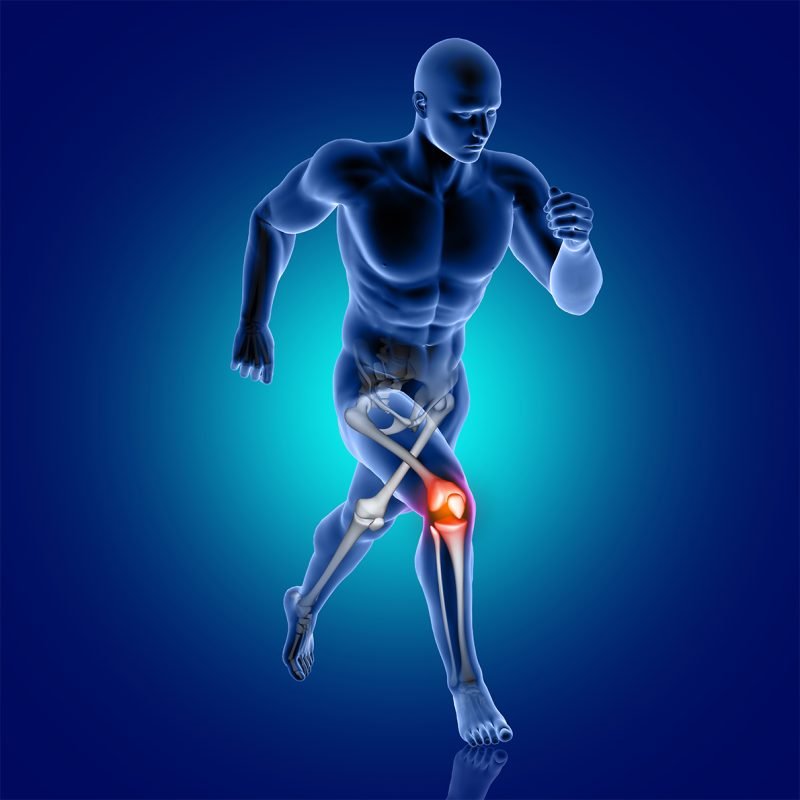

Knee Joint

Knee ACL tears, meniscus injury and patellar tendinitis are likely. Pain, swelling, and restricted movement may be the results of sudden twists, running, or jumping.